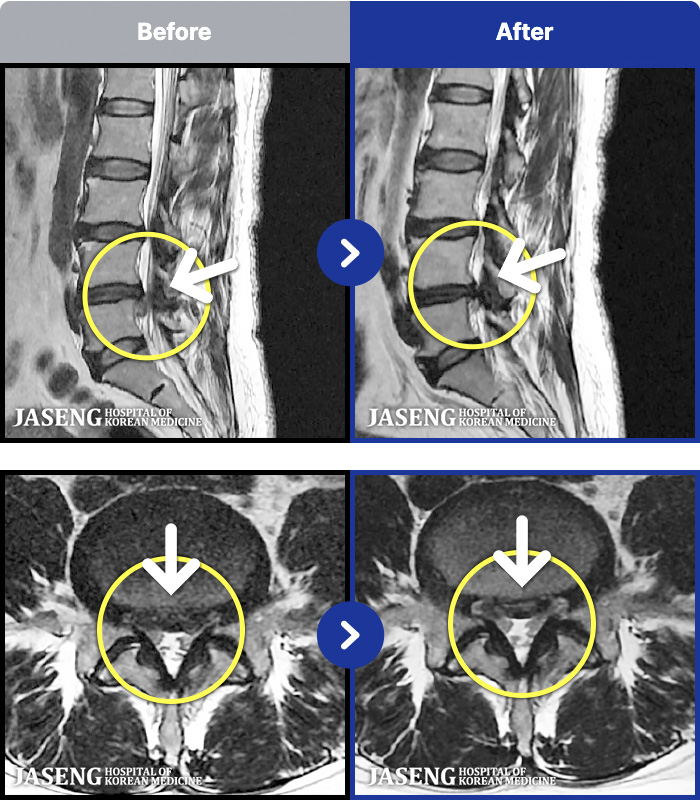

[뱸] 19.11.28~25.05.06

ȯںп Ǹ ǿ ԿǾ, ο ġ ۿ Ƿ ġḦ Ͻñ ٶϴ.